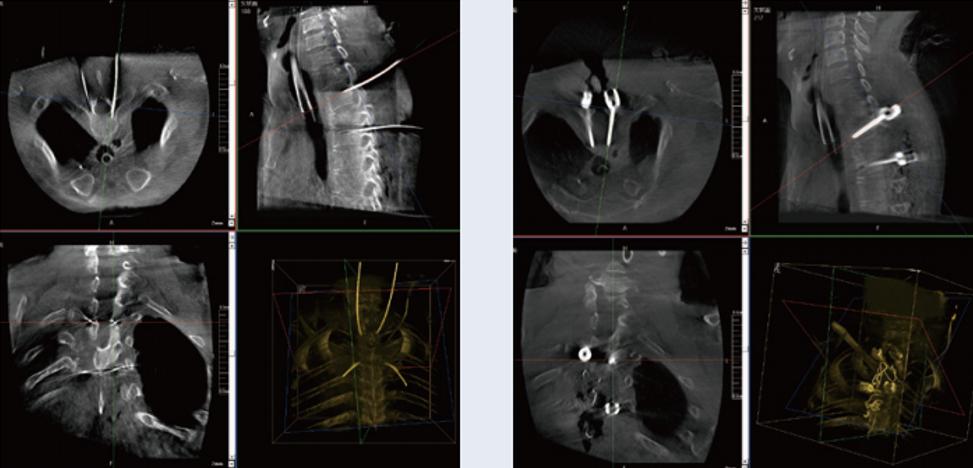

螺钉规划后的图像

植入螺钉后的图像

术中三维C形臂与脊柱导航机器人配合应用,实现准确定位,确保了手术安全、高效完成。术后二维、三维影像显示手术效果良好,达到预期目的。

普爱医疗三维C形臂提供了高质量的术中实时三维图像数据,保障了脊柱导航机器人手术的准确度和安全性,取得不错的手术效果。同时,术中三维C形臂特有的断层成像,能帮助医生在术中非常直观地判断螺钉植入的准确度。